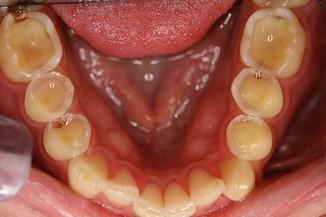

- Tooth Decay - Tooth Decay (dental caries), is a loss of tooth structure caused by bacteria breaking down sugars and the subsequent release of acids. If tooth decay is left untreated, it can cause severe pain and swelling, resulting in tooth loss.  - Tooth Decay happens as a result of several factors, including bacteria (plaque), sugar intake frequency and time*. - Bacteria - microorganisms that can digest sugars from your diet - Sugar - source of energy that bacteria needs to grow and cause decay - Time - tooth decay is a long-term process and doesn't happen overnight - *If you remove one or more of these factors, tooth decay may be preventable and even stop progressing entirely.  - There are many patterns of tooth decay, and the exact size/depth can be unpredictable.